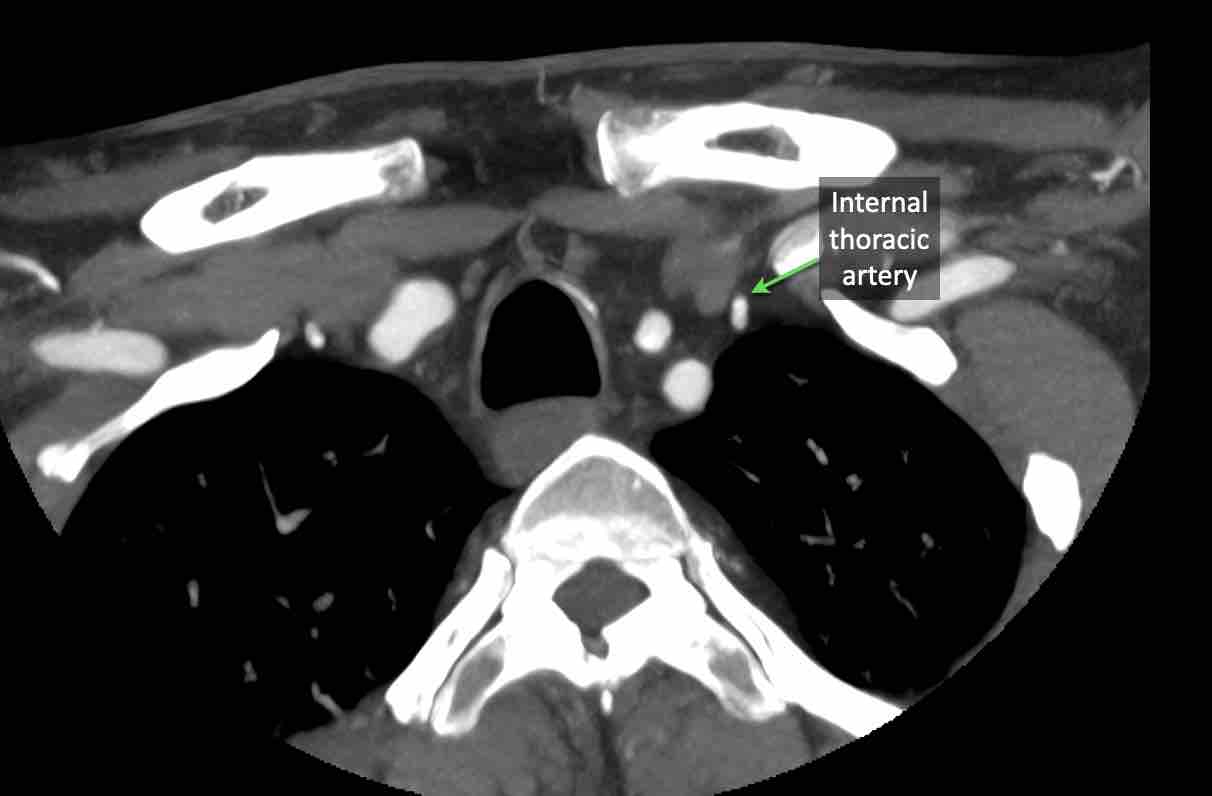

Động mạch cổ ngang

Cuộn qua các hình ảnh để xem giải phẫu của động mạch cổ ngang.